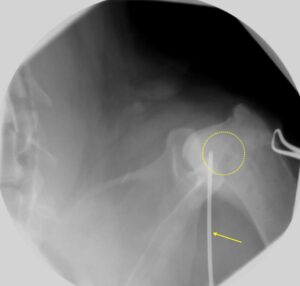

骨肉腫の確定診断には基本的には骨生検が必要です。ジャムシディ骨髄生検針や骨生検鉗子を用いて骨組織を採取します。病変部位が不明瞭な場合には、透視レントゲン装置やCTガイド下で組織生検を行います。

*透視レントゲンガイド下での骨生検(黄色点線丸が病変、黄色矢印が生検鉗子)

*骨生検鉗子